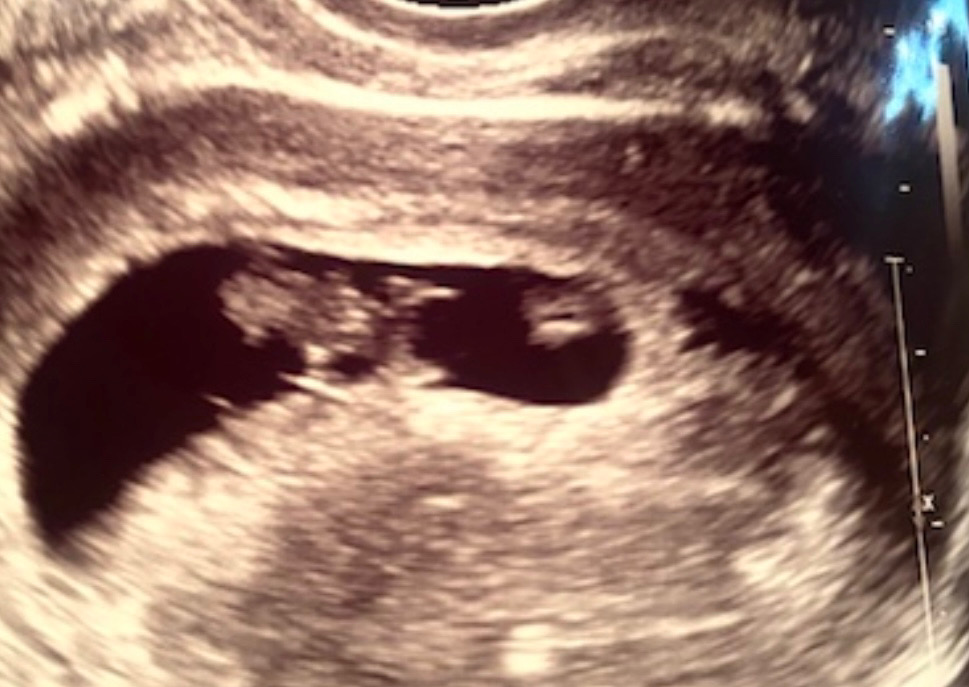

첫 초음파(8주)

첫 초음파하고 왔어요…. 임신 알게되고 첫 초음파 하기까지 보낸 지난 4주가 4년같았달까요….그래도 사이즈도 심장박동도 모두 정상적으로 잘 자라고 있다는 말에 너무 안심이 되고 감사했어요…뭔가 태아도 기다렸다는듯이 활짝 반겨주는 느낌? 한국이랑 다르게 미국 병원은 여러모로 느리고 절차가 많아 답답하기도 했지만 그래도 오늘은 기분이 너무 좋네요~~!! 그렇게 기다리던 심장박동 소리 듣는데ㅠㅠ눈물이 핑돌더라구요. 이제 또 다음 병원방문은 4주 뒤라는데 이번엔 4달 같은 4주가 될듯해요 ㅎㅎ 궁금한건 분명 병원에서 여기가 머리다 어디다 라고 설명들었는데… 사진으로 받아 집에 오니 헤깔리네요 ㅎㅎ 그리고 오른쪽 동그란건 몰까요?……….아깐 안보였는데 지금은 보이는 ㅎㅎㅎㅎ혹시 보시고 아시는분….